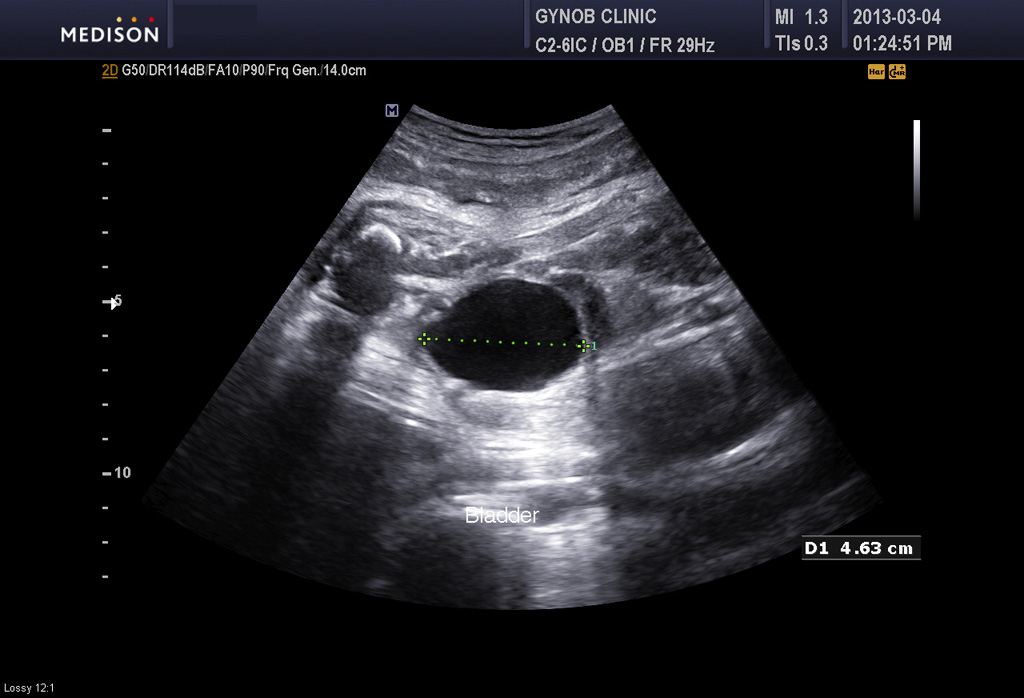

그런데 그 산모는 초음파 검사상 태아의 방광이 수시간 동안이나 비워지지 않고 꽉 찬 상태로 보여 혹시 태아의 비뇨기 계통의 기형인 "요관 말단 판막 (posterior urethral valve)"이라고 하는 기형이 있지 않은가 하는 의심이 들었습니다.

요관 말단 판막은 그리 흔한 기형은 아니지만 남자 아기에게서 주로 생기고 방광의 소변이 원활하게 체외로 나오지 못하는 기형입니다.

따라서 그런 기형이 있을 경우 방광은 많이 커지고 양수는 줄어들게 됩니다.

콩팥도 영향을 받는 경우가 많은데 그 산모의 태아는 콩팥은 이상이 없어 보였지만 경미한 타입의 판막증에서는 그럴 수도 있기 때문에 태아의 건강을 생각하여 산모와 상의하여 대학 병원에서 출산하기로 결정을 하였습니다.

아래 사진은 그 산모분의 산전 진찰시 초음파 사진인데 위는 양소 과소증을 나타내 주는 사진이고 아래는 태아 방광의 사진입니다.